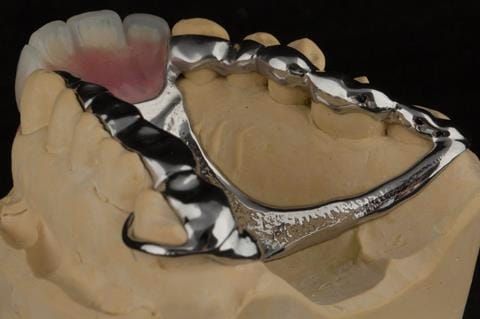

- Extract the upper 2-2 teeth and replace with an interim acrylic based partial denture. Reline the interim denture over 9 - 12 months, replacing with a definitive cobalt chromium based partial denture. The definitive denture would ideally be designed as an occlusal protective splint to reduce the the potential for mechanical wear and breakages of the moderately/heavily restored maxillary dentition. In addition, should further upper teeth require extraction they could be added on to the denture cobalt chromium framework - therefore a new prosthesis would not be required as future teeth are lost. This option would produce an excellent aesthetic outcome. This is the option the patient chose to have.

Following consultation and second discussion appointment the patient chose to have option 3 namely, a maxillary cobalt chromium based partial denture/protective occlusal splint. The clinical situation and treatment process is shown in detail below with photographs. The patient was successfully rehabilitated with this and her quality of life considerably improved. The clinical work was provided by Finlay and the technical work by Rowan.